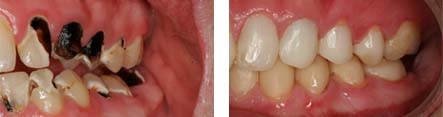

Crown